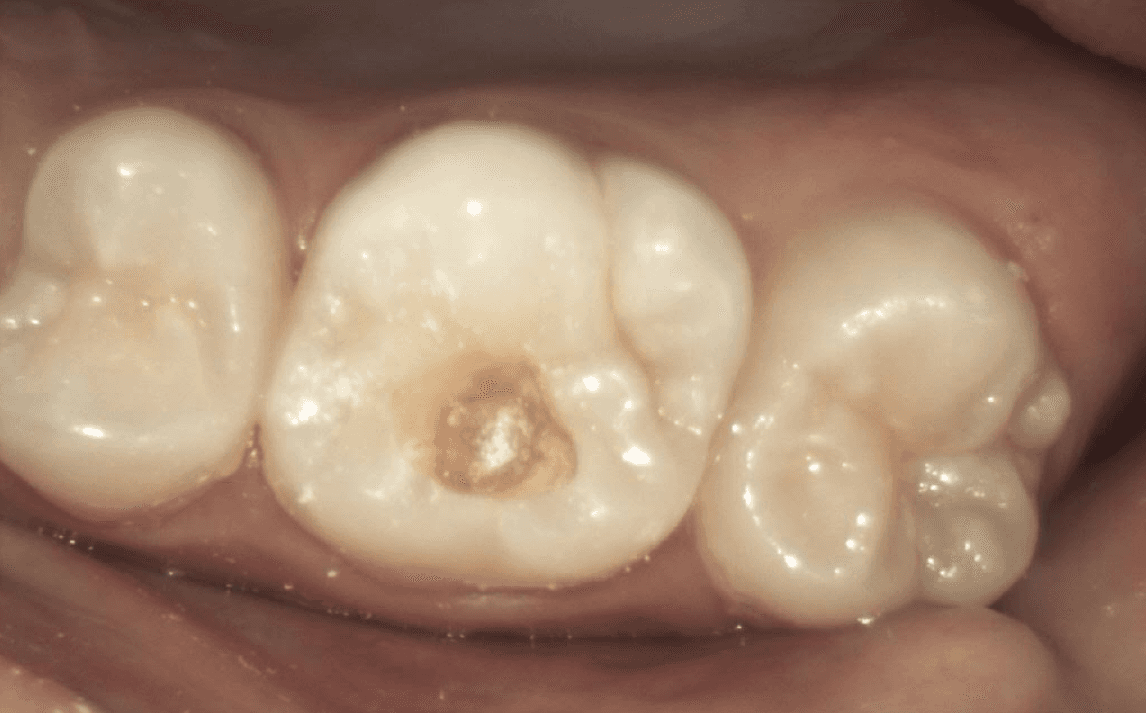

Take a look at the following example:

Decay was confirmed